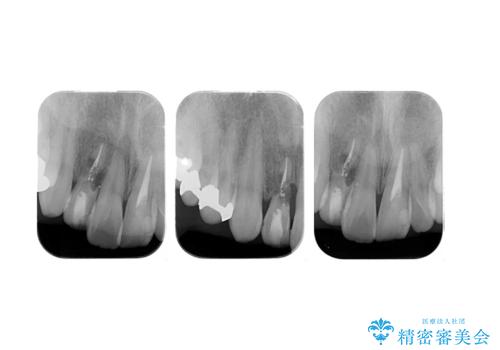

- 他院で右上の前歯の状態が悪いことを指摘されて来院。

昔ぶつけてしまった既往がありました。

歯の根の部分が内部で吸収し、周りの骨も吸収してしまっていました。

このまま放置すると、骨の吸収も進行し、いずれ近い将来歯が折れてしまう可能性もありました。また、隣の歯にも骨の吸収による影響が始まっており、持たせるだけ持たせたとしても次のステップの時には状況が悪化してしまうことが予想されました。